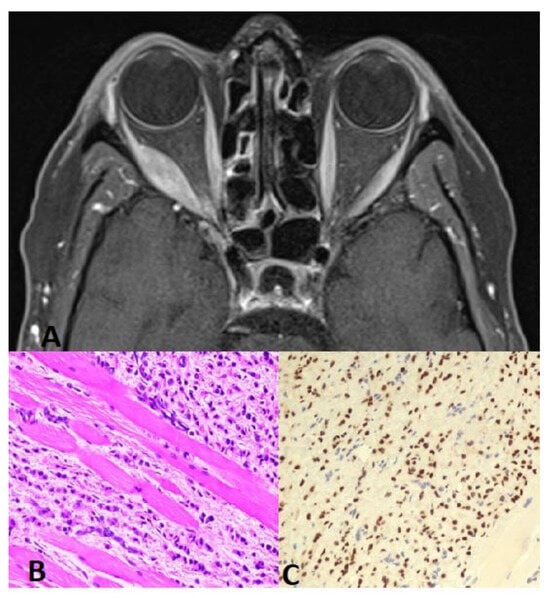

Figure 1. (A) Orbit CT axial scan shows soft tissue mass with involvement of the right lateral rectus muscle and extension into the right periorbital space. This is associated with partial encasement and displacement of the right optic nerve and mild proptosis. (B) Muscle biopsy: H&E 20× higher magnification reveals metastatic lobular carcinoma of the breast infiltrating the skeletal muscles. Note the linear/single-cell file arrangement of tumor cells (Indian-file pattern). (C) GATA3 20× tumor cells show nuclear positivity for GATA3 immunostain, confirming breast origin.